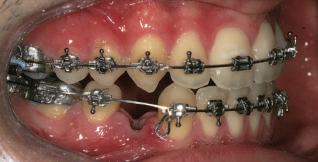

20 Dental Tribune Bulgarian Edition / октомври 2022 г. П ациентите със завършен растеж и скелетни проблеми обикновено представляват предизвикателство за ортодонт ската практика. Необходимостта от изваждане на зъби в комбинация с особеностите на възрастовата ортодонтия изисква особено внима ние. Фокусът върху критично важното значение на позицията на долните резци във връзка с дългосроч ната стабилност и постигането на оптимални оклузални взаимоотношения при затварянето на екстракционните пространства лесно може да излезе извън контрол. Когато към тези чисто кли нични проблеми се добави и стресът от натоваре ната практика, предизвикателството става още по-голямо. Всички тези фактори налагат използ ването на доказан подход с ясни и последовател ни стъпки, в което се разкрива силата на дисциплината „Алекзандър“ – предвидим протокол през целия процес на елиминиране на ротациите, ниве лиране на дъгите, затваряне на екстракционните пространства и финализиране на случая. Именно такъв е и случаят, който презентираме –екстракционен, скелетен клас 3 при възрастен па циент, лекуван по системата „Алекзандър“. ПРЕДВИДИМИ РЕЗУЛТАТИ ПРИ ПАЦИЕНТИ СЪС ЗАВЪРШЕН РАСТЕЖ И СКЕЛЕТЕН КЛАС 3, ИЗПОЛЗВАЙКИ ЕКСТРАКЦИОННО ЛЕЧЕНИЕ ПО ДИСЦИПЛИНАТА „АЛЕКЗАНДЪР“ Д-р Радой Димитров, България Преди започване на лечение клиничен случай | ортодонтия Фиг. 1а–1e Преди започване на лечение. Пациентът пристига в практиката с основното оплакване от невъзмож ност за нормално дъвчене. Снета е цялата необходима диагностична ин формация. Фиг. 1f–1h Снимки в профил и анфас. Фиг. 1i–1k Панорамна снимка, телерентгенография и анализ на телерент генография. Фиг. 1а Фиг. 1d Фиг. 1f Фиг. 1g Фиг. 1h Фиг. 1e Фиг. 1b Фиг. 1c Фиг. 1i Фиг. 1j Фиг. 1k

closed.

21Dental Tribune Bulgarian Edition / октомври 2022 г. ДИАГНОСТИЧНИ РЕЗУЛТАТИ: 1. Възраст на пациента: 21 години 2. Скелетен клас III (ANB 0) 3. Зъбен клас 3 4. Ръбцова захапка във фронта, кръстосана в дисталните участъци 5. Тясна горна челюст 6. Overjet – 0 мм, Overbite – 0 мм 7. Несъответствие на горната с долната средна линия 8. Единични контакти в ЦО 9. Хиподивергентен тип на растеж SN/MP – 33.5 10. Неравен гингивален контур 11. Неравна линия на усмивката 12. Тенденция за рецесии в долен фронт ПРЕПОРЪЧИТЕЛНО ЛЕЧЕНИЕ: Пълно ортодонтско лечение с метални брекети „Алекзандър“ Корекция на клас 3 захапката в областта на кучешките зъби с екстракция на първите пре молари в долна челюст Корекция на кръстосаната захапка в дистални участъци Коригиране на ръбцовата захапка във фронта Подобряване на ОJ и OB на пациента Стрипинг в долен фронт Подреждане на зъбите в горната и долната челюст Професионално хигиенизиране и профилактични дентални прегледи са препоръчителни на всеки 6 месеца. 1-ви месец След 1 месец са залепени брекети в горната челюст – поставена е еластична дъга. 016 NiTi. В долната челюст са елиминирани ротациите, поставена е стоманена дъга. 016SS, закалена с ток, и еластична верижка за затваряне на пространствата. 3-ти месец В долната челюст е поставена трета дъга – 17 x 25 NiTi с къси лигатури и верижка

В горната челюст се затварят пространствата с дъга .016SS и верижка. 5-и месец На 5-ия месец след залепяне на брекетите в долната челюст е поставена стоманена дъга 16 x 22 SS с четвъртито сечение, омега луп и тай бек. В горната челюст е поставена дъга 17 x 25 NiTi. Поради липсата на стабилни оклузални контакти са поставени лингвални верижки в областта на моларите, за да се предотврати нежелана ротация на 7-ите зъби. 6-и месец На 6-ия месец от началото на лечението са екстрахирани долните първи премолари, поставена е дъга 16 x 22 SS със затваряща чупка teardrop. Чупката се активира всеки месец по 1 мм с чинч-бек. клиничен случай | ортодонтия СТЪПКИ НА ЛЕЧЕНИЕТО Начало на лечението Лечението започва с поставяне на апарат за бърза експанзия в горната челюст. През първия месец от лечението са направени 24 оборота на апарата за експанзия. Залепени са брекети в долната челюст, поставена е дъга 17x25 CuNiTi, като са предпи сани клас 3 ластици (1/4”,4 1/2 oz) по време на сън, за да се осигури контрол върху торка на долните резци. Фиг. 2а Фиг. 3a Фиг. 4a Фиг. 3b Фиг. 4b Фиг. 3c Фиг. 4c Фиг. 3d Фиг. 4d Фиг. 3e Фиг. 4e Фиг. 5a Фиг. 5b Фиг. 5c Фиг. 5d Фиг. 5e Фиг. 6a Фиг. 6b Фиг. 6c Фиг. 6d Фиг. 6e Фиг. 7a Фиг. 7b Фиг. 7c Фиг. 7d Фиг. 7e Фиг. 2b Фиг. 2c Фиг. 2d